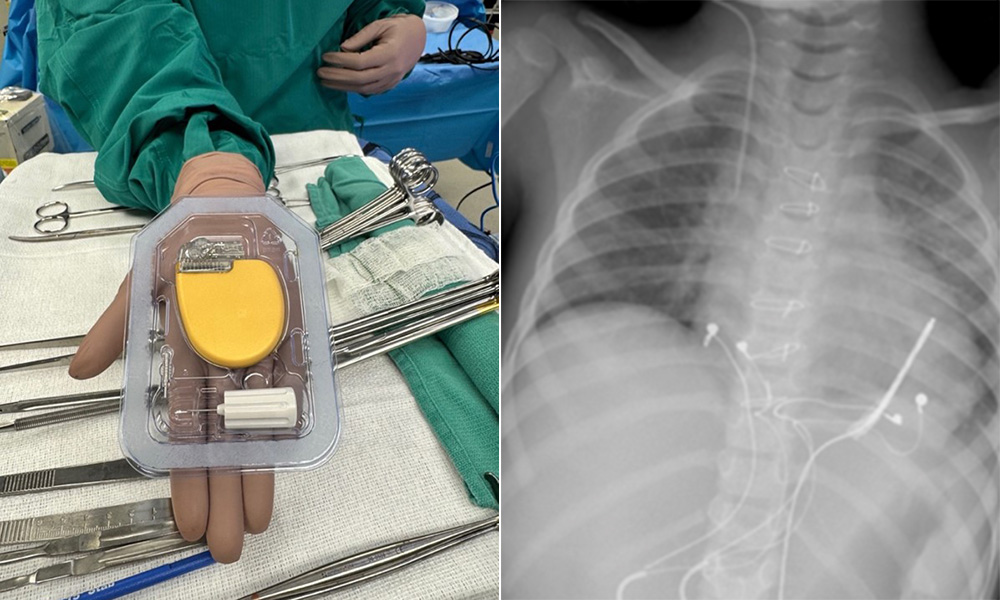

Racing back stronger: How a heart procedure put a NASCAR driver back in the driver’s seat